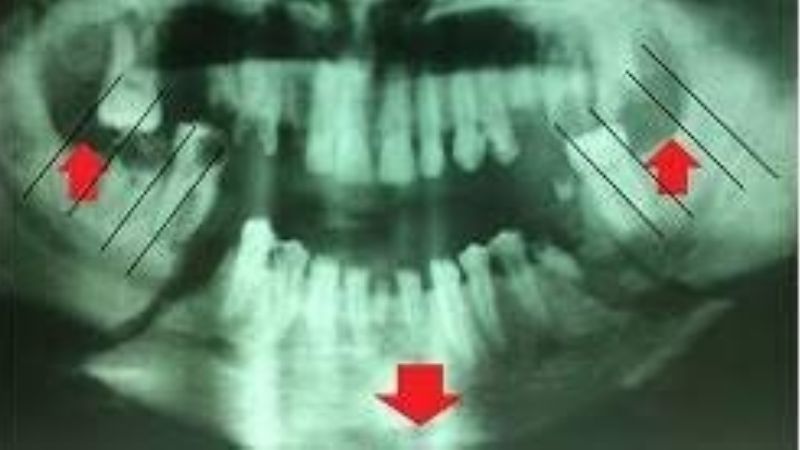

El caso ocurrió en febrero pasado, cuando el culpable le propinó dos golpes de puño en el rostro a su pareja provocándole una grave fractura de su mandíbula con deformación de rostro, tal como lo muestra la radiografía practicada a la víctima y que fue expuesta durante el juicio.